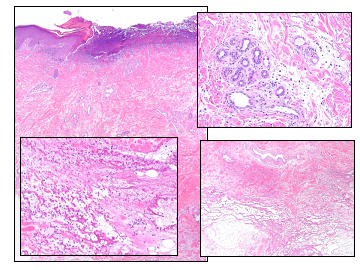

methotrexate_toxicity